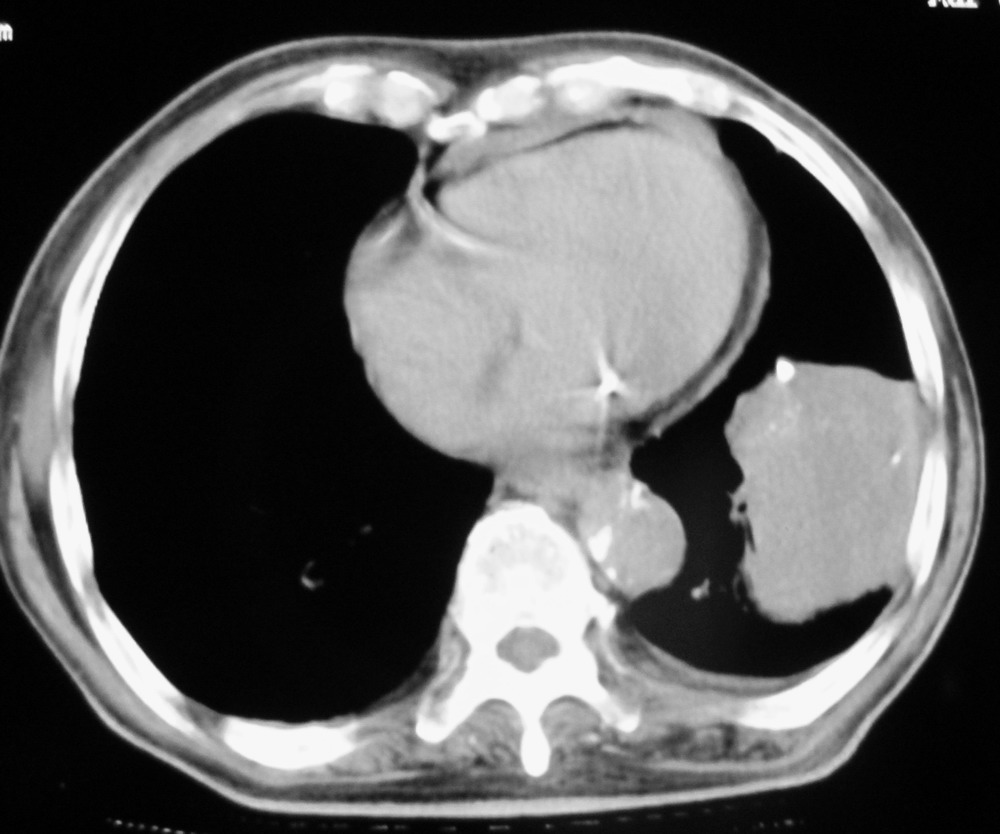

女,78,胸痛3个月,余无特殊。

1)左肺下叶软组织肿块,不排除周围型肺癌可能。2)左侧少量胸腔积液。3)心包积液。4)冠状动脉及主动脉钙化。

结果:肺癌